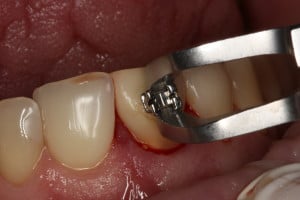

Przykład ekstruzji ortodontycznej za pomocą płytki termoformowalnej i zameczka ortodontycznego: